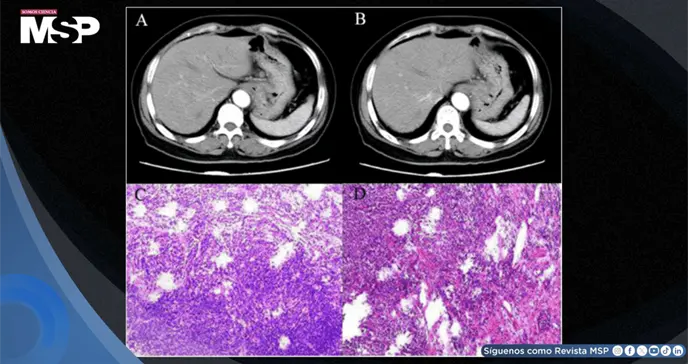

Para investigar la causa de sus síntomas, a la paciente se le realizó una tomografía computarizada (TC) abdominal con contraste. Las imágenes revelaron un engrosamiento anormal de la pared del estómago, específicamente en la región del cardias, el fundus y el cuerpo gástrico.

Además, se observaron múltiples metástasis en los ganglios linfáticos localizados entre el hígado y el estómago, así como en el espacio retroperitoneal. Estos hallazgos radiográficos fueron altamente sugestivos de una lesión maligna gástrica invasiva, con infiltración de la capa muscular profunda de la pared del estómago y la presencia de un trombo tumoral vascular.